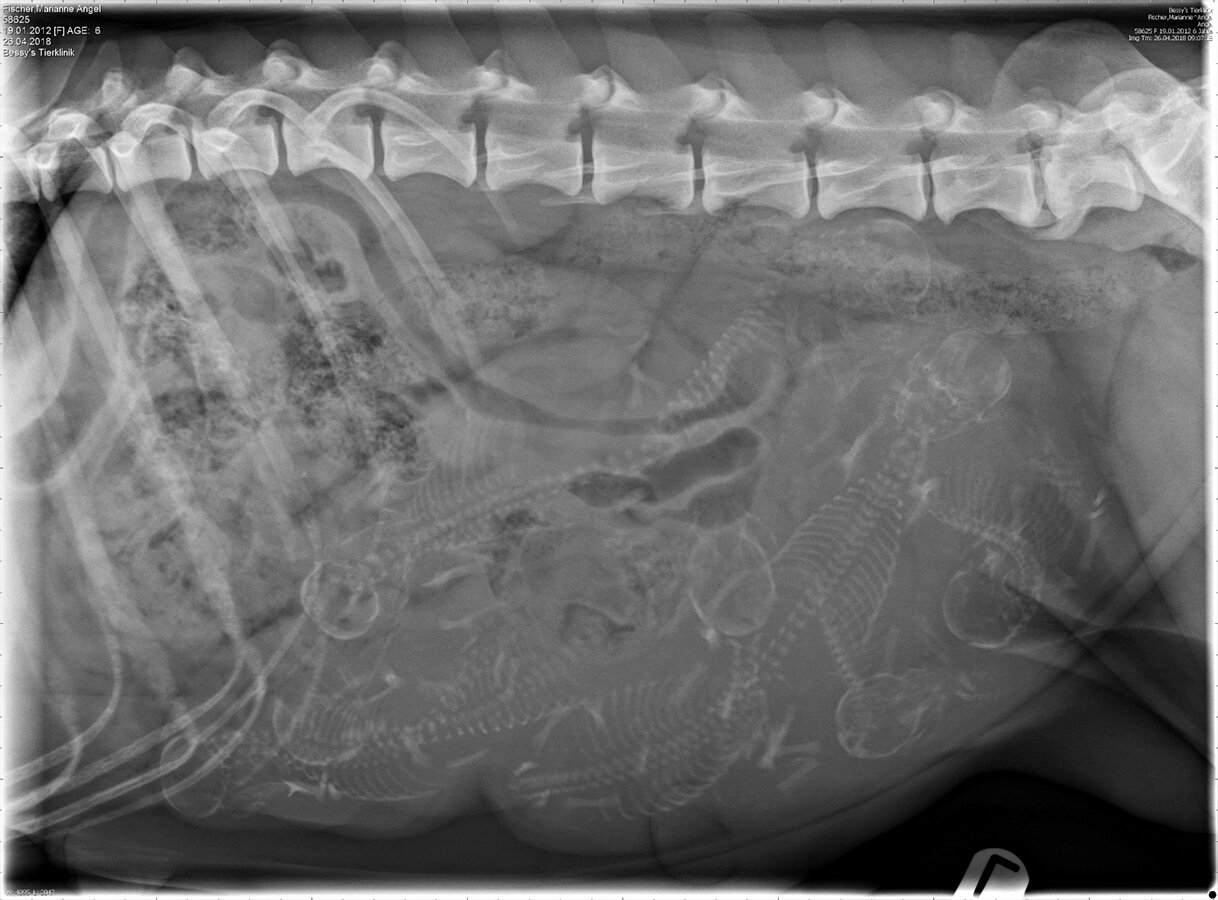

Beim heutigen Trächtigkeits-Röntgen hat sich das kleine Geheimnis offenbart, das Angel noch vor uns verborgen hat! Im Ultraschall vor 4 Wochen, konnten wir 7 Embryos zählen und jetzt im Röntgenbild, gut eine Woche vor dem errechneten Geburtstermin, kam noch ein 8-tes zum Vorschein!

Nun hoffen wir auf eine problemlose Geburt und auf 8 gesunde Welpen!